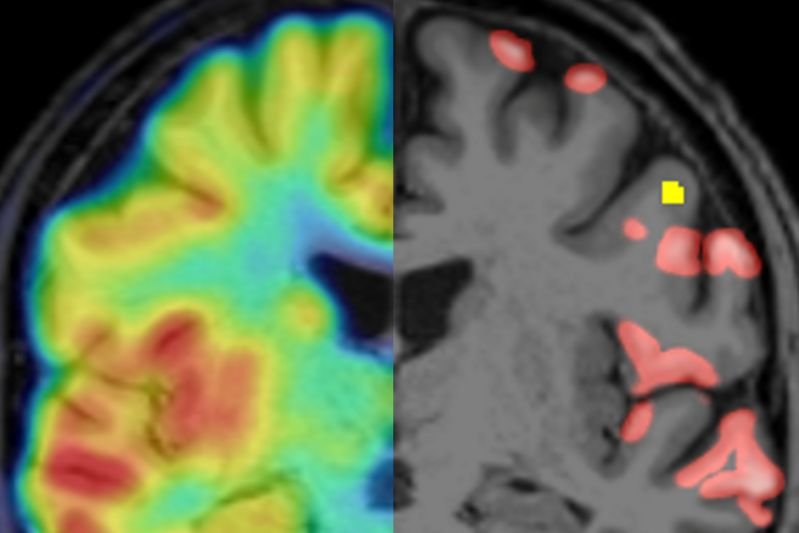

Überlagerung von Synapsen PET und MRT (links) und segmentierte Regionen mit cortikalen Läsionen in der MRT (gelb) sowie reduzierter Synapsendichte (rot)

Überlagerung von Synapsen PET und MRT (links) und segmentierte Regionen mit cortikalen Läsionen in der MRT (gelb) sowie reduzierter Synapsendichte (rot), LMU KLinikum

In Deutschland leiden etwa 250.000 Menschen an der Multiplen Sklerose. Es handelt sich um eine Autoimmunerkrankung, bei der die Körperabwehr Strukturen des Zentralen Nervensystems angreift. Die Attacken führen auch zu Veränderungen in der grauen Substanz im Gehirn - die Masse der Nervenzellkörper und Nervenzellverbindungen (Synapsen), die sozusagen unser “Rechenzentrum” bilden. Bislang gibt es keine Methode, um diese krankhaften Läsionen der grauen Substanz verlässlich und aussagekräftig nachzuweisen. Nun aber haben Forschende des LMU Klinikums erstmals gezeigt, dass sich mit der Positronen-Emissionstomografie der Synapsenverlust in den MS-Läsionen der Großhirnrinde abbilden lässt.

Kann ein anderes bildgebendes Verfahren, die PET, helfen? Dazu müsste man ein Protein der Nervenzellen finden, das sich einerseits mit diesem Verfahren nachweisen lässt und andererseits wertige Aussagen über die Dichte der Neuronen bzw. ihrer Synapsen liefert. In einer Serie von Experimenten bewies das Kerschensteiner-Labor zunächst, dass das Protein SV2A ein geeigneter Marker für die Synapsendichte bei MS ist. Anschließend hat das Team Mäusen, bei denen eine MS-ähnliche Entzündung der Hirnrinde ausgelöst wurde, eine schwach radioaktive Substanz gespritzt, die gezielt an SV2A andockt. Das strahlende Signal wird dann vom PET-Gerät erkannt. Zur Kontrolle und zum Vergleich wurden die Synapsendichten in denselben Läsionen mit etablierten Methoden gemessen. „So konnten wir zeigen, dass die mit PET-Bildgebung gemessenen Synapsendichten aussagekräftige Ergebnisse erzeugen“, erklärt Kerschensteiner, „bestätigt hat sich das auch in einer anschließenden Untersuchung mit gut 30 MS-Patienten.“